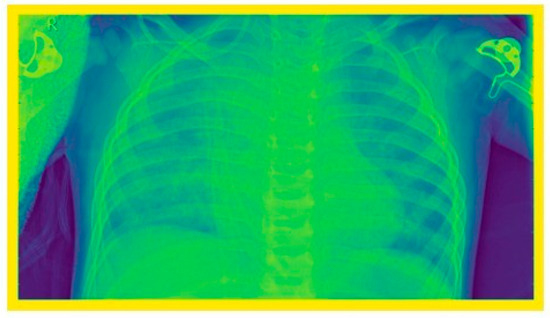

2.4. Image Enhancement Techniques